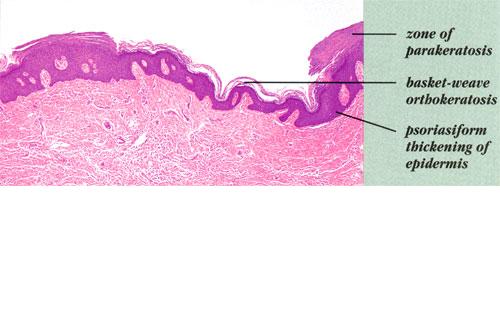

In the localized type, which is present usually but not invariably at birth, only one linear lesion is present. It consists of closely set, papillomatous, hyperkeratotic papules. It may be located anywhere-on the head, trunk, or extremities. Being located on only one side of the patient, it is often referred to as nevus unius lateris . In its configuration, the localized type of linear epidermal nevus resembles the inflammatory linear verrucous epidermal nevus (ILVEN), but the latter differs clinically by the presence of erythema and pruritus and histologically by the presence of inflammation and parakeratosis .

Histopathology.

Nearly all cases of the localized type of linear epidermal nevus and some cases of the systematized type show the histologic picture of a benign papilloma . One observes considerable hyperkeratosis, papillomatosis, and acanthosis with elongation of

Occasionally in cases of the localized type, but quite frequently in cases of the systematized type, particularly those with a widespread distribution, one observes the rather striking histologic picture referred to either as epidermolytic hyperkeratosis or as granular degeneration of the epidermis . It is the same process that was first recognized in all cases of bullous congenital ichthyosiform erythroderma, a disorder that is often referred to as epidermolytic hyperkeratosis . It has since been